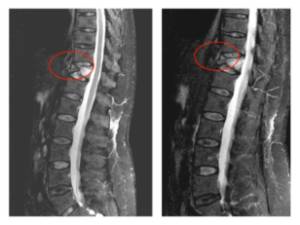

Pre- and post-operative comparison of a cemented kyphoplasty

Female, age 55, compression fracture of L2

Before 1

After 1

Before 2

after 2